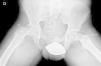

Diagnóstico por la imagenLas radiografías anteroposterior y axial de ambas caderas nos permitirán confirmar el diagnóstico. Es importante obtener la radiografía de ambas caderas por la alta incidencia de bilateralidad. En la radiografía antero-posterior y axial de ambas caderas podemos observar un desplazamiento antero-superior de la metáfisis proximal del fémur (cuello femoral) respecto a la epífisis (cabeza femoral). Denominamos signo de Steel, a la doble densidad radiográfica creada por la epífisis que se desplaza posteriormente y se superpone a la parte medial de la metáfisis (fig. 1). La línea de Klein, es una línea que se traza en la parte antero-superior del cuello femoral en la radiografía antero-posterior y que corta la epífisis. En los casos de ECF, la epífisis femoral queda por debajo de esta línea (fig. 2).

La gravedad de la ECF se mide de 2 maneras. El desplazamiento de la epífisis respecto a la metáfisis es el porcentaje de desplazamiento de la cabeza femoral respecto al cuello. Este desplazamiento puede ser leve (<33%), moderado (33–50%) y grave (>50%) (fig. 3). Aunque se utiliza de forma frecuente, presenta una gran variabilidad inter-intraobservador, además de estar influenciado por la posición del paciente. Southwick describió el ángulo epífisis-diáfisis en la radiografía anteroposterior y axial de ambas caderas. Se traza una línea a través de la superficie fisaria de la epífisis y se dibuja un ángulo recto a partir de esa línea. A continuación, se traza una línea paralela a la diáfisis del fémur. El ángulo formado por estas dos últimas líneas es la medida del desplazamiento posterior. Se resta el ángulo obtenido en la cadera sana del ángulo en la ECF, obteniendo así el grado de desplazamiento. El grado de deslizamiento se clasifica como leve (<30%), moderado (30–50%) y grave (>50%) (fig. 4).